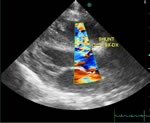

L'ecocardiografia evidenzia la presenza di un difetto interventricolare sottoaortico tra aorta e tricuspide con diametro superiore al 50% dell'aorta (Fig. 2), senza alcuna copertura aneurismatica, con sovraccarico di volume del ventricolo e dell'atrio sinistro; al color doppler ampio jet sinistro-destro a bassa velocità suggestiva per elevata pressione in ventricolo destro (Fig. 3).